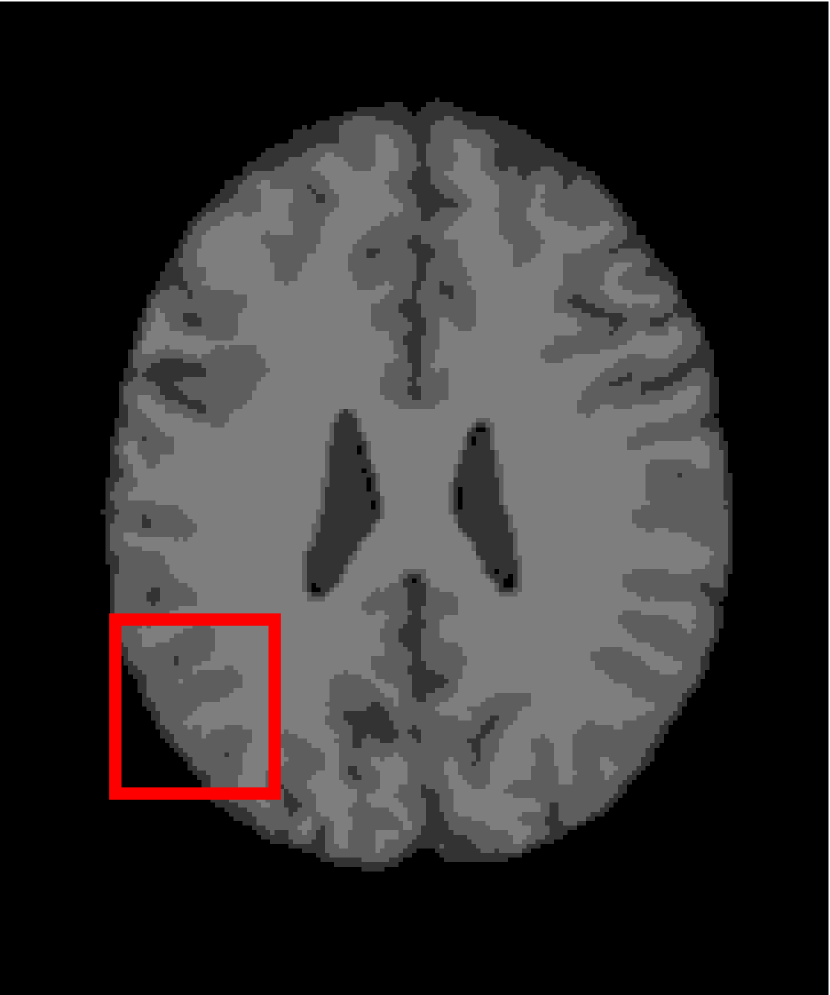

In the second experiments, we segment two medical images coming from a simulated brain database (BrianWeb): http://www.bic.mni.mcgill.ca/brainweb/. The two images are generated by T1 modality with slice thickness of 1mm resolution, 9% noise and 20% intensity non-uniformity. Here, the two images are represented two slices in the axial plane with the sequence of 100 and 110. Moreover, there are golden standard segmentations in the dataset. We set the numbers of clusters to 4. The visual comparisons are illustrated in Figs. 6 and 7.

Figure 6: Segmentation results for the first medical image. From (a) to (l): ground truth, noisy image and results of FCM_S1, FCM_S2, FGFCM, FLICM, KWFLICM, ARKFCM, FRFCM, WFCM, DSFCM_N, and LRFCM.

By focusing on the marked red square in Figs. 6 and 7, we easily find that FCM_S1, FCM_S2, FGFCM and ARKFCM are sensitive to noise. FLICM and KWFLICM are vulnerable to severe intensity inhomogeneity. FRFCM brings overly smooth results due to the use of gray level histograms. WFCM and DSFCM_N cause several contours to change. However, LRFCM acquires clear contours and suppresses noise adequately. Moreover, we find that the segmentation result of LRFCM is closer to ground truth.